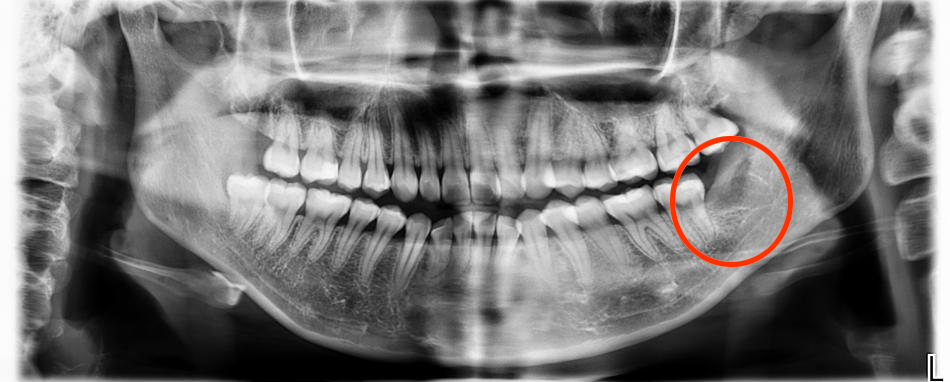

成功拔除智齿